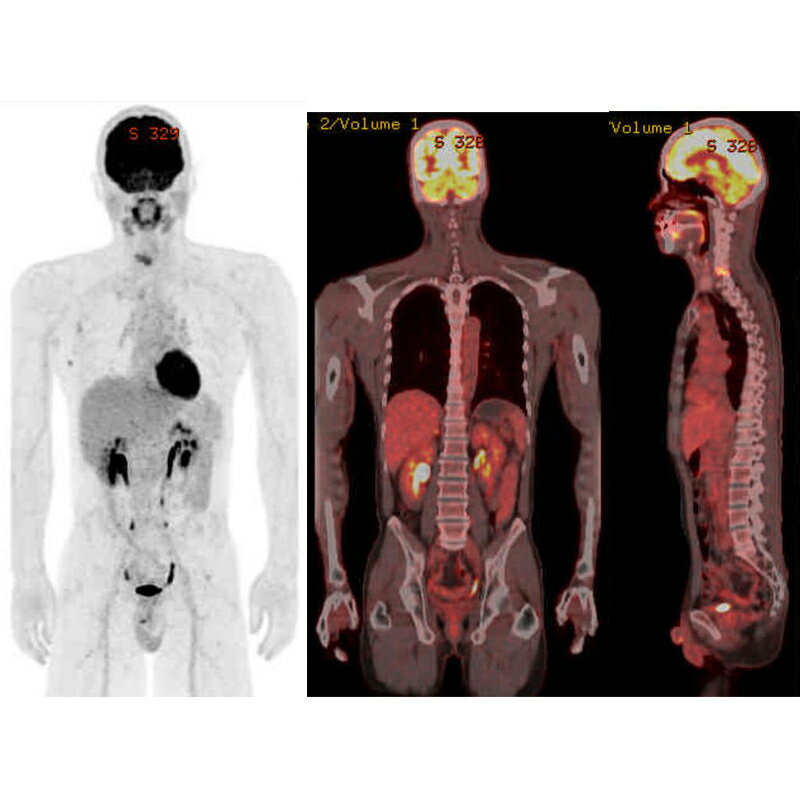

【ふるさと納税】佐久医療センター PET/CTがん検診 【佐久総合病院 PET/CTがん検診 がんの罹患数は多くのがんで増加 早期発見・早期治療ができれば転移や再発のリスクが少ないうちに治療ができる 治癒率(治る確率)が向上 長野県 佐久市 】